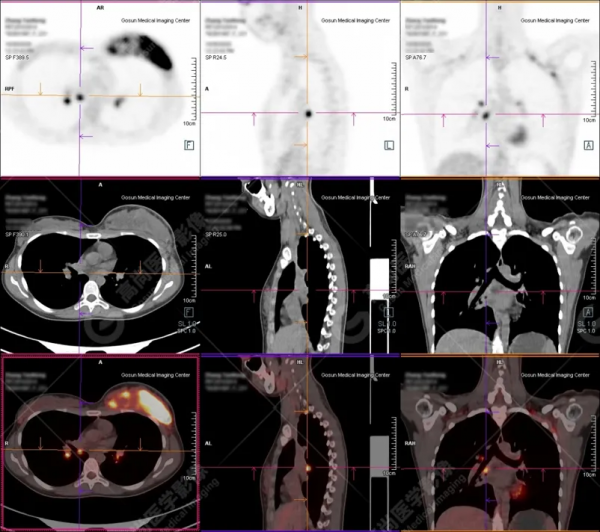

病例三

病史:患者27歲,年輕女性。

順產10月,戒奶後,發現乳腺硬塊入院檢查。

腫瘤標誌物均正常。

檢查所見:

PET/CT提示:

右側乳腺內散在多發不規則結節狀及片塊狀高代謝病灶,考慮為乳腺癌,浸潤相鄰面板可能。

右側鎖骨上區、右側胸肌間隙、右側腋窩及縱隔(2R組)多發增大淋巴結,伴代謝增高,考慮為轉移。

枕骨基底部、左側肱骨頭、胸骨、左側肩胛骨、雙側多處肋骨、脊柱大部分椎體及附件、骨盆諸骨及左側股骨頭多發骨轉移。

病理穿刺:

浸潤性腺癌。